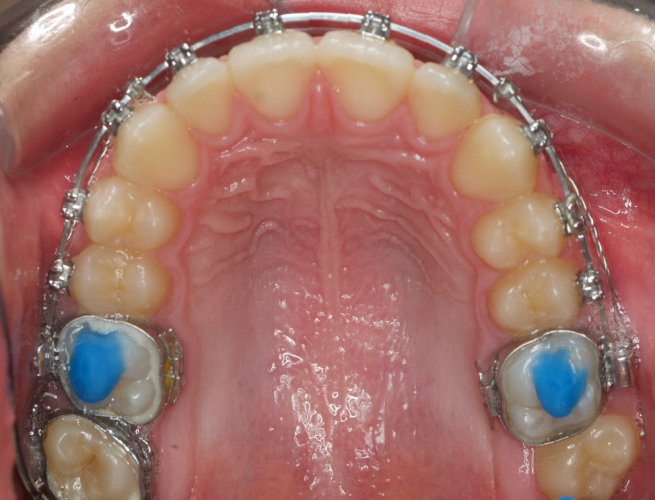

Paciente de 14 años, acude a nuestra consulta por dientes superiores proclinados hacia delante y apiñamiento. El paciente presenta una full clase 2, sobremordida y dientes inferiores proclinados. Decidimos colocarle brackets Damon y microtornillos en maxilar superior para distalizar las muelas. La duración del tratamiento fue de  24meses, y ahora lleva 1 año de contención. El paciente se pone la férula Essix superior 1noche/2 y la de abajo 1noche/semana para mantener.

DICIEMBRE 2013 - Upper Occlusal